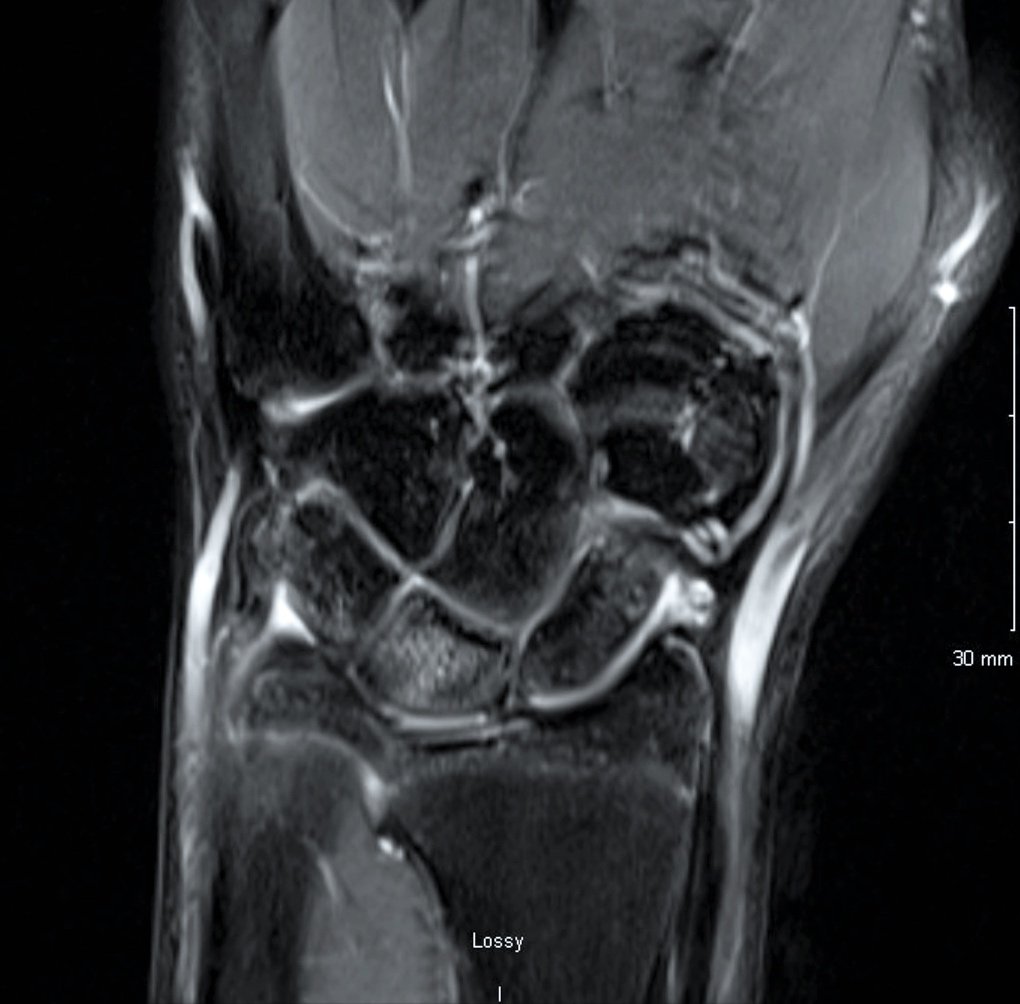

Ulnar positive variance

Signal changes (edema) in the lunate

IMAGING: X-rays will show an ulnar positive variance (see X-ray to the left). An MRI is not required for evaluation but will often show high signal in the lunate, indicating swelling (edema) in the bone from repetitive impacts from the distal ulna. TFCC tears are commonly seen.